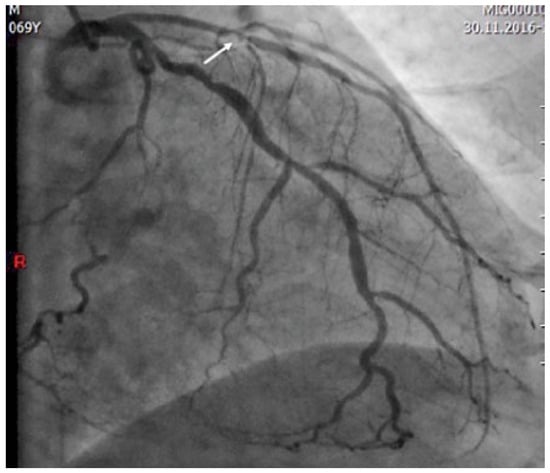

Two types of Wellens’ syndrome are identified. The most common (type I, 75% of cases) is characterised by deep negative T waves in V2–V3 and often in V4. One third of patients present the less common type II, with biphasic T waves in V2–V3 as seen in our patient [6,7]. Echocardiography on the day of presentation showed normal systolic function without regional myocardial motion abnormalities. A second troponin analysis was slightly positive. The patient underwent urgent coronary angiography (12 hours after the first medical contact), which showed severe multivessel coronary artery disease with a severe proximal LAD stenosis involving the ostium of a diagonal branch (Figure 2). Coronary by pass graft surgery was performed and the post-operative period was uneventful. On subsequent echocardiography, the systolic function was normal without regional wall motion abnormalities. Figure 3 shows the ECG after revascularisation.

Figure 2.

Coronary angiography demonstrating the critical proximal LAD stenosis involving the ostium of a diagonal branch (arrow).